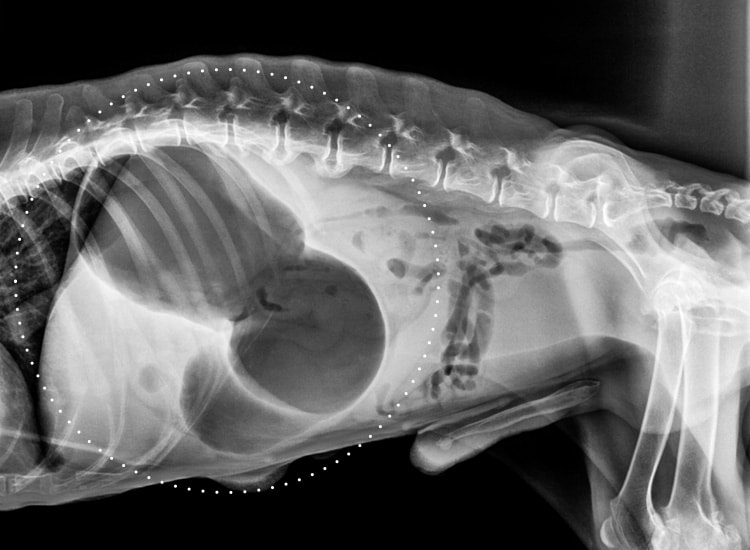

Radiographie d’une dilatation de l’estomac chez un chien

La torsion de l’estomac

L’estomac se retourne sur lui-même (généralement dans le sens des aiguilles d’un montre), provoquant alors une occlusion des voies d’entrée (au niveau du cardia après l’œsophage) et de sortie (au niveau du pylore conduisant à l’intestin).

La torsion a pour conséquence l’emprisonnant des aliments et des gaz qui ne peuvent plus ressortir de l’estomac.